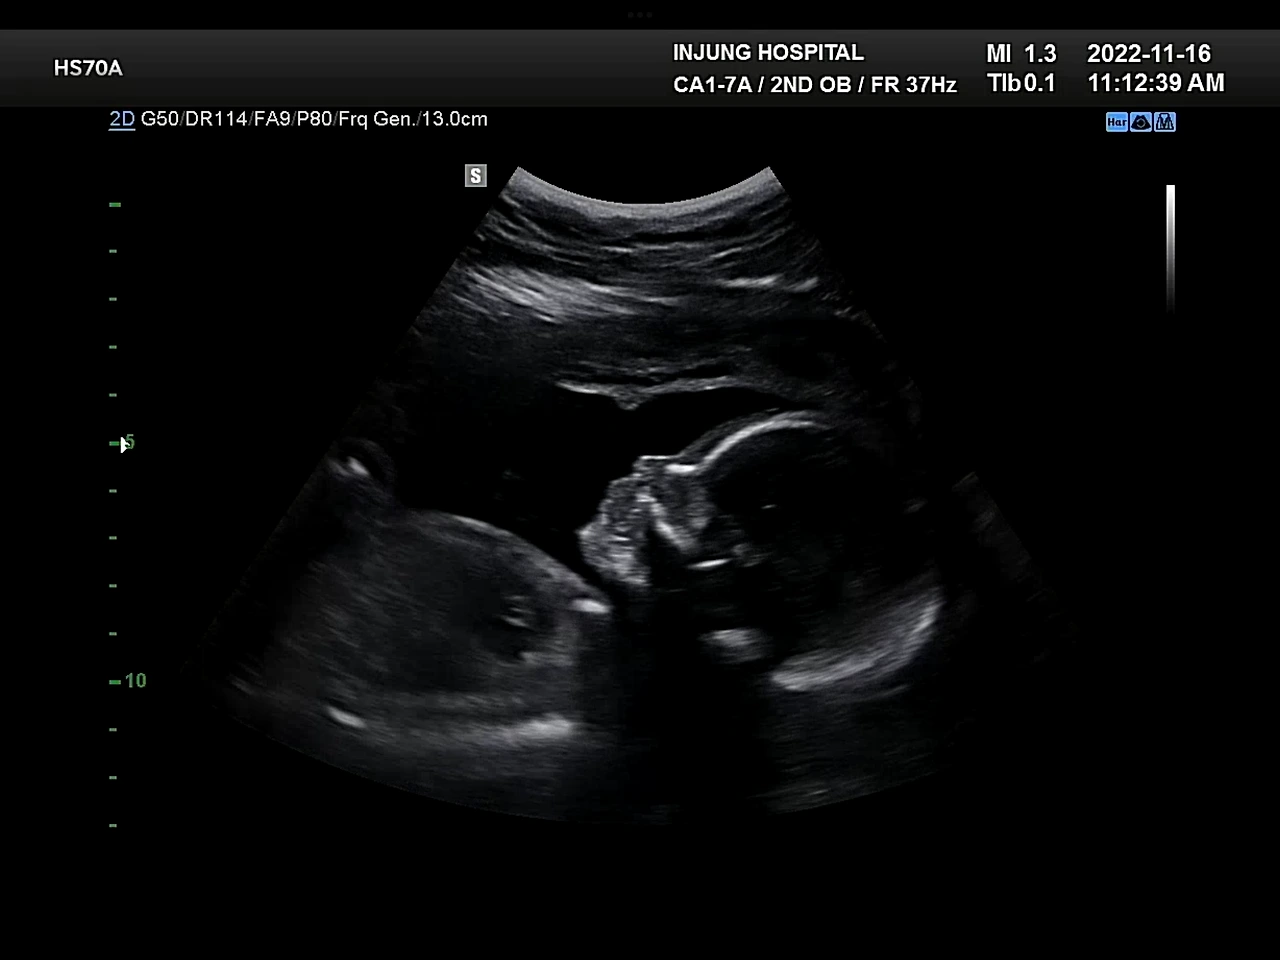

20주

태동이 부쩍 활발해졌다. 그러다가도 태동이 별로 안 느껴지면 잘 있나 싶어서 걱정이 되기도 했다. 포도는 그럴 때마다 내 불안한 마음을 잠재우기라도 하려는 듯이 힘차게 움직여주었다.

포도는 잘 있어요!